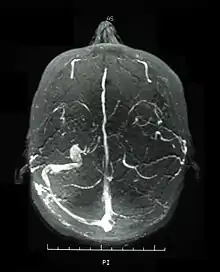

Visual acuity, or color vision loss with concurrent mucocutaneous lesions or systemic Behçet's disease symptoms should raise suspicion of optic nerve involvement in Behçet's disease and prompt a work-up for Behçet's disease if not previously diagnosed in addition to an ocular work-up. Diagnosis of Behçet's disease is based on clinical findings including oral and genital ulcers, skin lesions such as erythema nodosum, acne, or folliculitis, ocular inflammatory findings and a pathergy reaction. Inflammatory markers such ESR, and CRP may be elevated. A complete ophthalmic examination may include a slit lamp examination, optical coherence tomography to detect nerve loss, visual field examinations, fundoscopic examination to assess optic disc atrophy and retinal disease, fundoscopic angiography, and visual evoked potentials, which may demonstrate increased latency. Optic nerve enhancement may be identified on Magnetic Resonance Imaging (MRI) in some patients with acute optic neuropathy. However, a normal study does not rule out optic neuropathy. Cerebrospinal fluid (CSF) analysis may demonstrate elevated protein level with or without pleocytosis. Imaging including angiography may be indicated to identify dural venous sinus thrombosis as a cause of intracranial hypertension and optic atrophy.

In an epidemiologic study, 56 percent of patients with Behçet's disease developed ocular involvement at a mean age of 30.[45] Ocular involvement was the first manifestation of Behçet's disease in 8.6 percent of patients.[45] Ocular Behçet's disease with involvement of the optic nerve is rarely reported. Among patients with ocular Behçet's disease funduscopic findings of optic atrophy, and optic disc paleness have been identified with a frequency of 17.9 percent and 7.4 percent, respectively. Other fundoscopic findings include vascular sheathing (23.7%),[7] retinal hemorrhage (9%),[7] macular edema (11.3%),[7] branch retinal vein occlusion (5.8%),[7] and retinal edema (6.6%).[7] However, optic atrophy was the most significant cause of visual impairment identified in 54 percent of patients with ocular Behçet's disease and permanent visual impairment.[7]